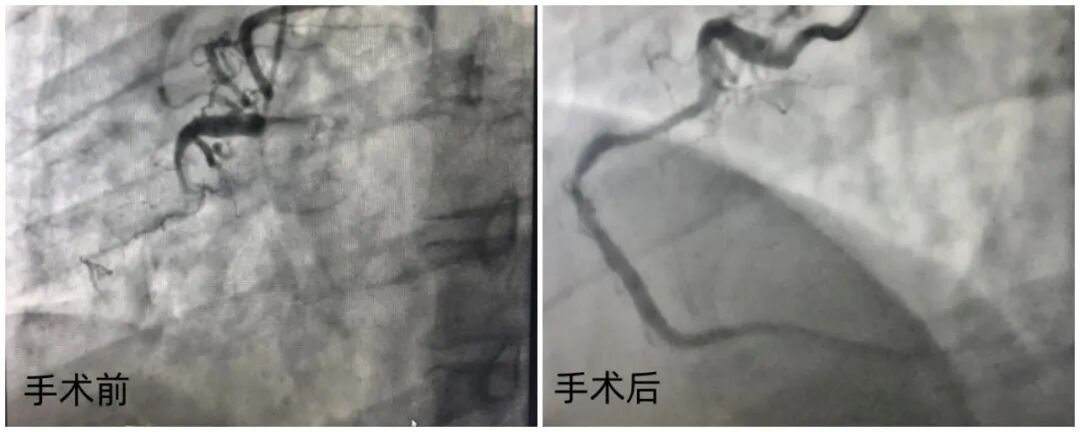

43岁的黄先生半年前开始频繁出现胸闷、胸痛症状,冠脉造影显示其前降支70-80%狭窄、回旋支远端次全闭塞,右侧冠状动脉近端更是完全闭塞,病情危急。

抵达阜外华中心血管病医院后,李牧蔚教授团队第一时间为黄先生完善了全面检查,而冠脉CTA结果显示,他的病情比预想中极为复杂:右冠状动脉近端和中远段存在两处长闭塞段,且整个血管走行极度迂曲、立体成角,给介入操作带来了极大挑战。

随后,她对狭窄病变部位进行小心翼翼的预处理,确保血管达到无明显狭窄、无中膜夹层的理想状态,再将药物球囊精准送达病变区域,让抗增殖药物均匀涂贴在斑块表面,从根源上抑制血管再狭窄。历经3个多小时的精细操作,手术顺利完成,黄先生的冠脉血管恢复通畅,自然构型与分支血流均得到完好保留。